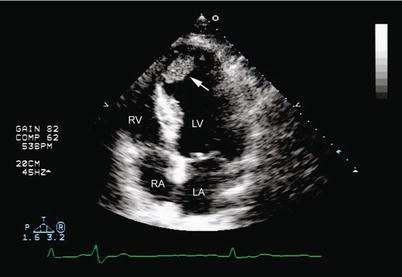

The coronary artery views obtained with epicardial imaging are dependent on the position and angulation of the probe on the heart. RECENT FINDINGS The high temporal and spatial resolution of tissue Doppler and strain rate imaging permit. Coronary arterial disease CAD constitutes the main cause of morbid-mortality in the modern world.

Echocardiography is a versatile imaging modality for the management of patients with chest pain and assessment of left ventricular systolic function diastolic function and even myocardial and coronary perfusion and is therefore useful in the diagnosis and triage of patients with acute chest. Lecture series Clinical Echocardiography. Echocardiography is the initial modality employed in the assessment of proximal coronary arteries in children Video 1. Detection of coronary artery lesions CALs at initial echocardiography can aid in diagnosing Kawasaki disease KD and inform primary adjunctive treatments. Coronary arterial disease CAD constitutes the main cause of morbid-mortality in the modern world. This study investigated the diagnostic role of layer-specific analysis using 2-dimensional speckle-tracking echocardiography STE during DSE. 1 However echo images may be sub-optimal in older patients with high body mass indices. Echocardiography in Coronary Artery Disease inproceedingsGlobits2000EchocardiographyIC titleEchocardiography in Coronary Artery Disease authorS. Coronary artery lesions prevalence at initial echocardiography consistently increased after the fifth day of illness and was higher in patients with Kawasaki disease aged 0 to 5 months and 60 months compared with those at intermediate months of age describing a Ushape trend.

The coronary artery views obtained with epicardial imaging are dependent on the position and angulation of the probe on the heart. The clinical utility of echocardiography across the spectrum of coronary artery disease has been well established by a large number of studies Table 1. Confira as ofertas para livros em inglês e importados. Coronary artery disease CAD is one of the major causes of morbidity and mortality. 1 However echo images may be sub-optimal in older patients with high body mass indices. Role of echocardiography in patients with coronary artery disease. In Brazil according to the data of the Health Ministry it is responsible for approximately one million hospitalizations and 25 of deaths that occur annually 1.